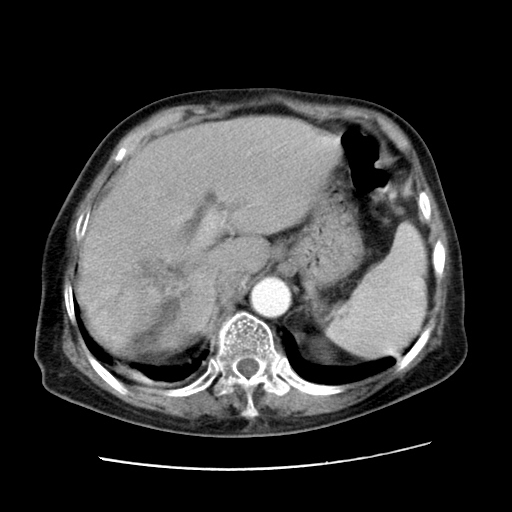

标题: CT25203:上腹部增强,看看

女,77.无不适

肝脏变异、异位胆囊,肝右叶肝内胆管结石并肝内胆管扩张。

肝内胆管扩张,胆囊炎,胆囊窝积液。 右侧胸腔少量积液。

肝右叶肝内胆管结石并肝内胆管扩张。

肝右叶肝内胆管结石并肝内胆管扩张

肝右叶肝内胆管结石并肝内胆管扩张。另:慢性胆囊炎!胆囊窝积液!

右侧肝内胆管局限性扩张,其内密度不均匀,扩张的胆管壁增厚,考虑肝内胆管炎合并结石可能性大